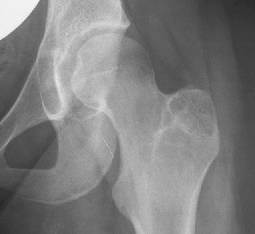

Periprosthetic Tibial Fractures In Total Knee Arthroplasty An Outcome Analysis Of A Challenging And Underreported Surgical Issue Bmc Musculoskeletal Disorders Full Text